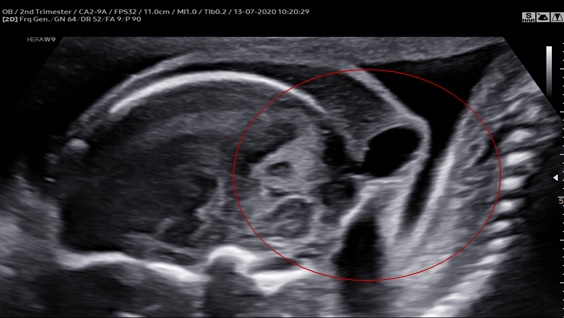

Thai phụ 32 tuổi, PARA 1021, lần đầu tiên đến khám tại bệnh viện Từ Dũ lúc thai 23 tuần. Siêu âm ngã bụng với máy WS80 (Samsung). Quan sát thấy các bất thường: đầu thai nhi ngữa với cổ gập ra sau cố định, cằm đưa ra trước và liên tục với ngực bởi lớp da, thoát vị màng não, thể chai dày, thiểu sản thùy nhộng, nếp gấp da gáy dày, bàn tay tư thế bất thường, cấu trúc “đuôi” ở vùng cùng cụt. Siêu âm chẩn đoán: Dị tật khuyết ống thần kinh thể Iniencephaly. Thai phụ được tư vấn chấm dứt thai kì sau đó.

Hình 1: Mặt cắt dọc cho thấy cổ gập sau sát với cột sống và thoát vị màng não ở xương chẩm.

Hình 2: Mặt cắt ngang cho thấy thoát vị màng não, nếp gấp da gáy dày

Ca của chúng tôi có đầy đủ các đặc điểm của một Iniencephaly thể hở: thoát vị màng não, đầu cỗ ưỡn cố định ra sau, da vùng cằm liên tục với ngực, cột sống cổ biến dạng và hợp nhất một cách bất thường.